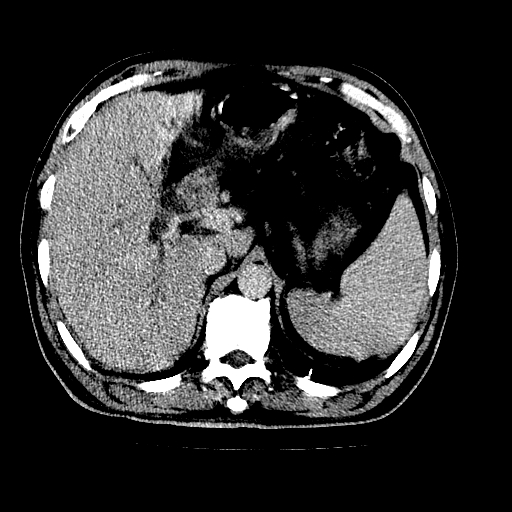

男,66岁,上腹部不适、黄染一周。彩超示:肝左叶占位,肝内胆管扩张,胆总管扩张,胆总管占位?

肝左叶不规则软组织肿块影,边缘不规整邻近肝实质受累分界不清;肝内胆管(左叶)明显扩张成“软藤状”,诊断:肝左叶胆管细胞癌。

支持肝左叶肝内胆管细胞癌伴胆总管及门脉左支受侵。

胆囊缩小,其内胆汁浓缩,也提示梗阻部位应该位于胆囊管起始部以上或是胆囊管受累及,支持肝外胆管癌。